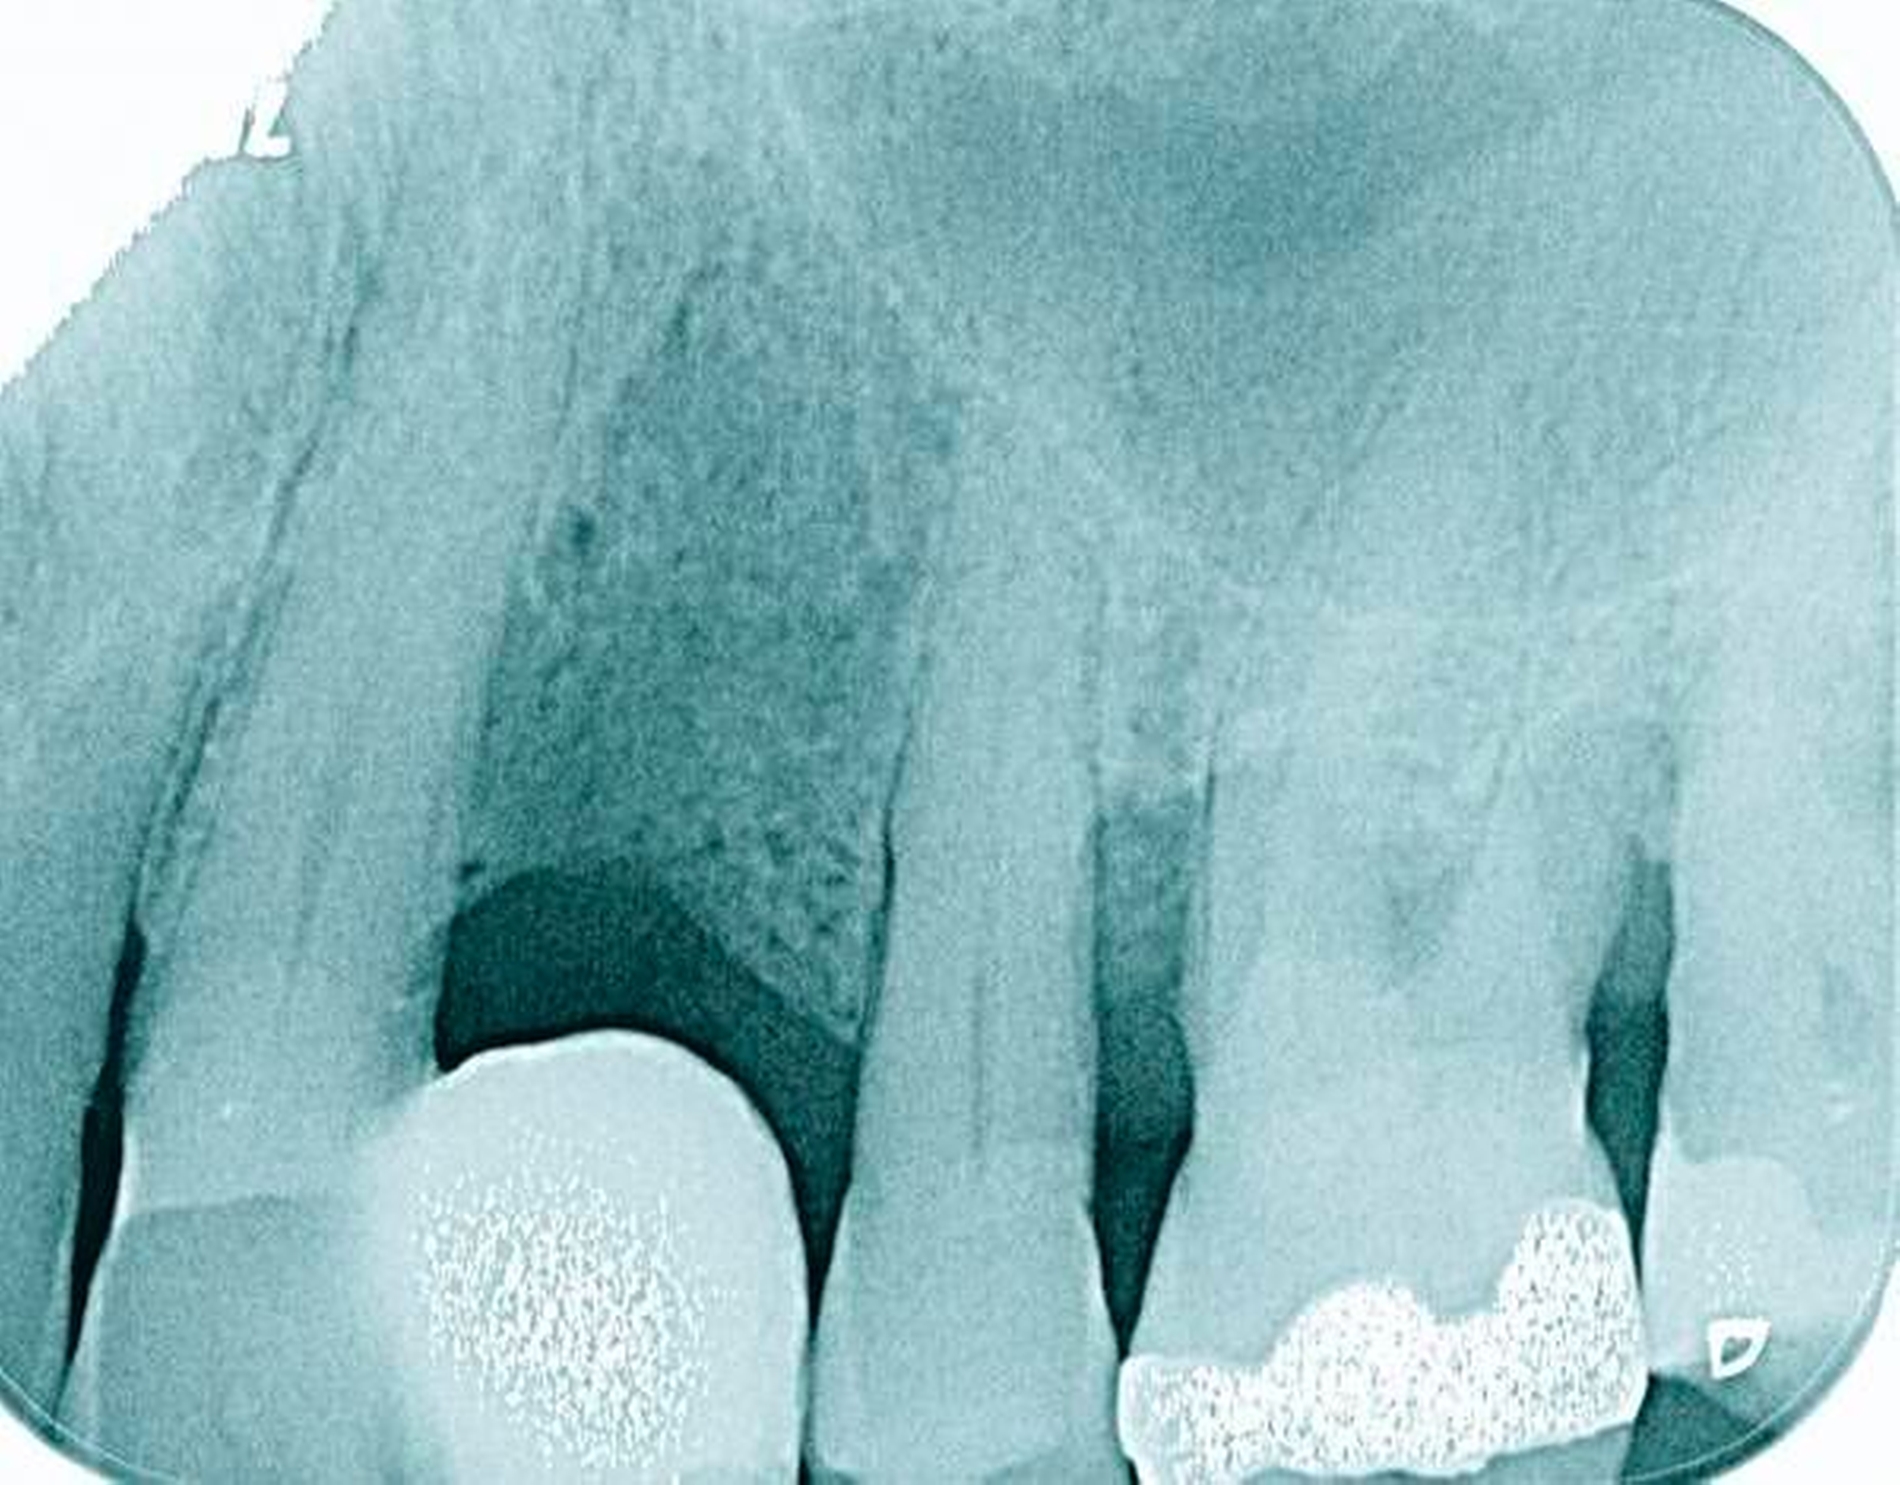

In den Abbildungen 1 bis 3 werden Optionen für frugale Interventionen auf restaurativem Sektor aufgeführt. Es handelt sich um direkte Vollüberkronungen im Frontzahnbereich (hier: hergestellt in R1-Technik / einphasig) (Abbildung 1), direkte Teilüberkronungen im Seitenzahnbereich (hier: hergestellt in R1-Technik / einphasig) (Abbildung 2), Reparatur-Restaurationen im Seitenzahnbereich (hier: hergestellt in R2-Technik / zweiphasig) (Abbildung 3). Technische Einzelheiten zur Vorgehensweise und den Ergebnissen sind an anderer Stelle beschrieben (Literatur siehe oben).

Für die in Abbildung 2 dargestellte Situation eines tief zerstörten Prämolaren gelten ähnliche Charakteristika. Es gibt in der restaurativen Zahnheilkunde viele Neuerungen, die das Behandlungsspektrum vergrößert haben. Dazu zählen unter anderem:

ein- oder zweiphasiges Vorgehen je nach Defektausdehnungen (R1- und R2-Technik),

von Präparationsgrenzen unabhängige Verschalungstechniken, die auch bei nicht-kariesbedingten Zahnhartsubstanzschäden (wie etwa Hypomineralisationen) zum Einsatz kommen können,

schadensgerechte Reparaturtechniken (Abbildung 3),

neuartige Insertionstechniken, die unter anderem die Anpassung neuer Restaurationen an vorhandene prothetische Versorgungen (Reziproktechnik) erlauben.